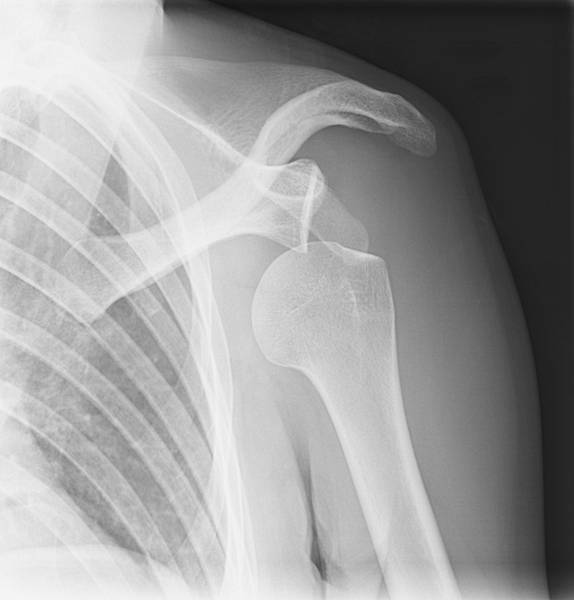

脫臼發生的當下,多半是劇烈的運動傷害或交通意外,在肩關節強力外展及外轉的狀態下受傷,外觀上看起來肩關節會往內縮,此時要高度懷疑肩關節發生脫臼,搭配X光檢查若顯示肩關節脫臼,必須盡快進行肩關節復位,肩關節復位是分秒必爭的醫療處置,當肩關節處在脫臼的狀態,時間一長,相對較硬的肩胛骨會在肱骨頭留下不可復原的骨頭缺陷(Hill Sach lesion),有這樣的狀況 其脫臼復發比率大增。有些骨質比較差的患者,可能合併骨折的發生,有時需要電腦斷層來幫助釐清病情。另外有些病患表現則是肩關節半脫位,X光並不會看到有典型脫臼表現,症狀很可能只是疼痛或是描述運動時肩部完全使不上力,這時候,理學檢查就極為重要,理學檢查可能發現肩關節在內轉的活動度變少,以及當病患做出肩外轉的動作,肩部前方會有疼痛,病患會有恐懼害怕脫臼重現的感覺,當醫師把手加壓在肩部前方處,病患疼痛會緩解。